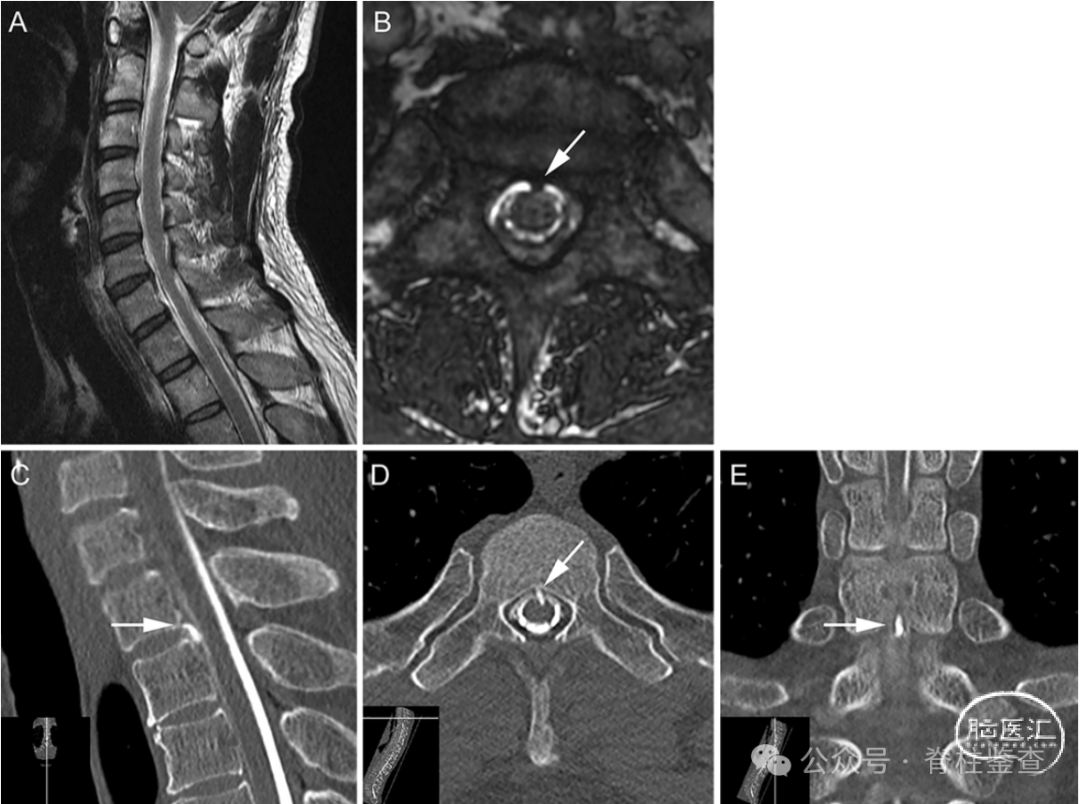

Case 1

45 岁男性因自发性低颅压导致严重直立性头痛就诊。

经硬膜外修复手术后,患者症状完全恢复。

A:MRI T2矢状面显示硬膜外积液;B:轴位图像显示T1/2水平有棘状突起(箭头)。C-E:脊髓造影CT矢状位、轴位和冠状位显示侧硬膜中央高密度毛刺状病变(箭头)。